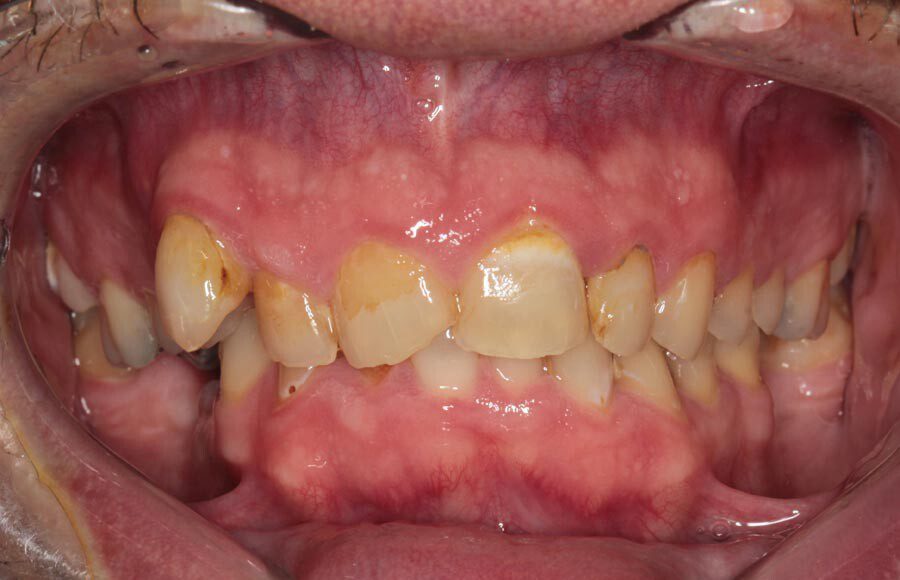

Smile GalleryImplant RestorationsImplant Dentures Post-op smiling 1 of 32 Pre-op close up smiling Pre-op lips retracted smiling Pre-op panoramic x-ray Implants in upper jaw (occlusal view) Implants in lower jaw (occlusal view) Panoramic x-ray of implants First set of try-ins – upper denture First set of try-ins – lower fixed provisional Delivered try-ins (lips retracted) Close adaptation to gums and appropriate emergence profile of lower fixed provisional Gum tissues have been molded by a convex provisional Delivered try-ins Second set of try-ins (lips retracted) Close adaptation to gums and appropriate emergence profile of second set of lower fixed provisional Delivered second try-ins Definitive restorations on casts (frontal view) Definitive restorations on cast (right side) Definitive restorations on cast (left side) Definitive upper overdenture (occlusal view) Definitive lower fixed titanium-acrylic hybrid restoration (occlusal view) Definitive lower fixed titanium-acrylic hybrid restoration (frontal view) Definitive lower fixed titanium-acrylic hybrid restoration (tissue side view) Healthy molded gum tissues on lower prior to delivery of lower fixed hybrid restoration Healthy gum tissues on upper prior to delivery of upper overdenture Definitive restorations (frontal, lips retracted) Definitive lower restoration (frontal) Definitive restorations (right side) Definitive restorations (left side) Definitive lower restoration (occlusal view) Definitive upper restoration (occlusal view) Post-op panoramic x-ray Post-op smiling